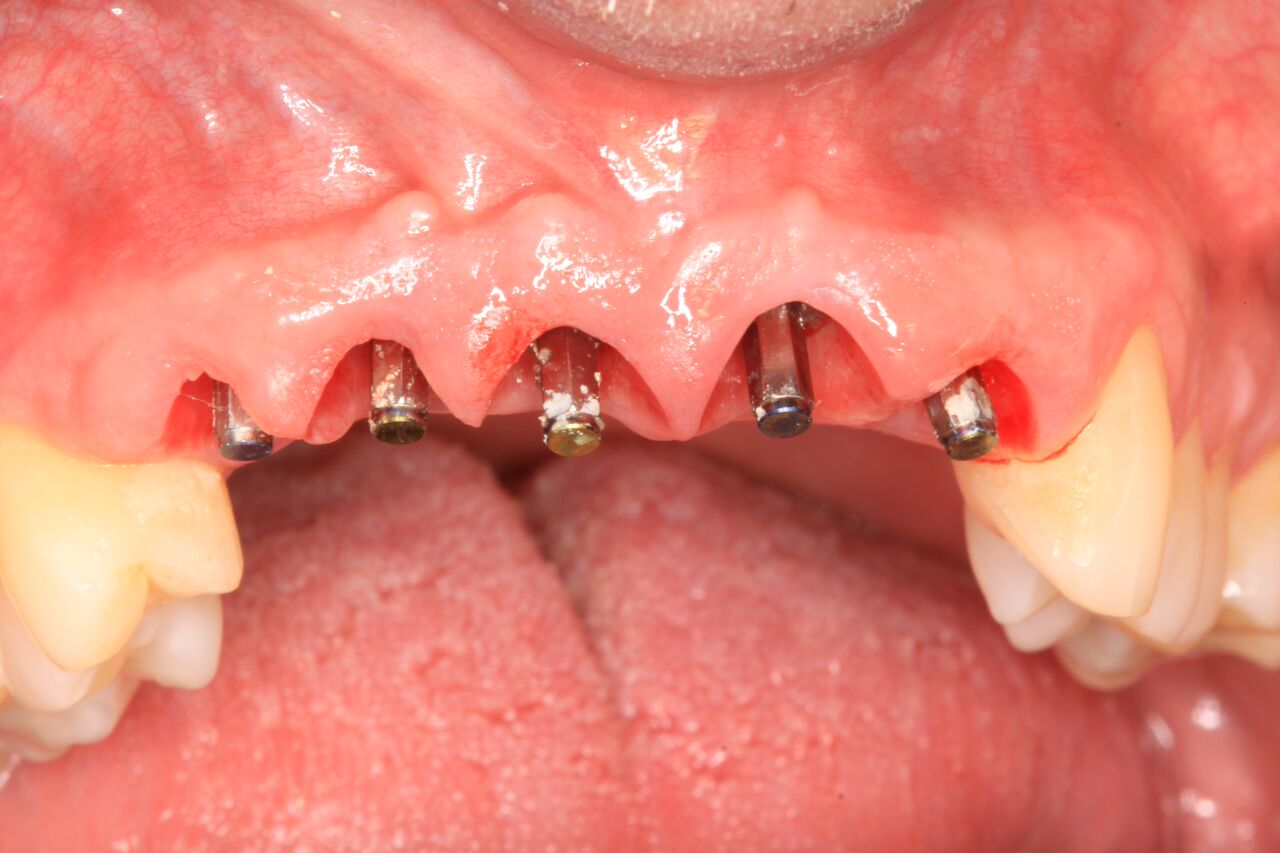

(22.) Temporary crowns on Nos. 6 through 10 at integration confirmation.

Figure 22

(23.) Soft tissue maturation at integration confirmation at 6 months.

Figure 23

A 42-year-old man presented with a very loose bridge on Nos. 6 through 9 with periodontally compromised retainers on Nos. 6 and 9 (Figure 17 through Figure 19), and endodontically involved No. 10 with a calcified canal. Teeth Nos. 6, 9, and 10 were extracted, the sockets fully debrided, and pontic soft tissue on Nos. 7 and 8 sculpted to be symmetrical in soft tissue contour with the contralateral lateral incisor and central incisor locations. Implants were secured in position Nos. 6 through 10 (Figure 20) in excess of 45 Ncm, the bone was milled to provide unimpeded seating of temporary abutments, and temporary crowns were fabricated chairside and adjusted to be out of occlusion in centric relation and all excursions. The temporary crowns were cemented after extrusion of excess cement extraorally and the patient was prescribed antibiotics, analgesics, and instructed in postoperative care particular to immediately provisionally restored implants. At 6 months, integration was confirmed (Figure 20 through Figure 23) and after placement of scanning abutments, the implants and soft tissues were scanned. Final crowns were fabricated from the scanned images and were cemented after extrusion of excess cement extraorally (Figure 24 through Figure 26), and oral hygiene procedures were reviewed.